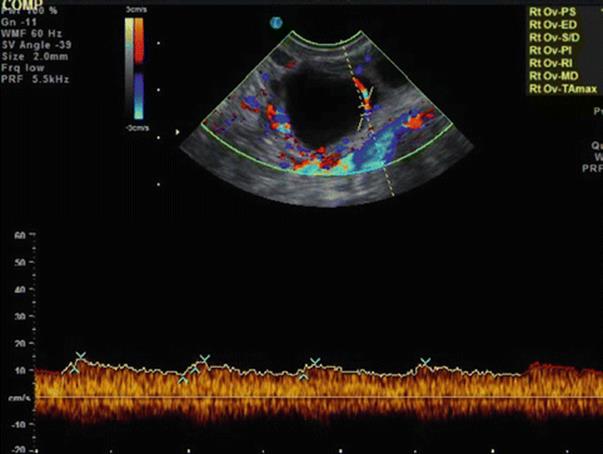

Using color Doppler, one can detect the vascularity of the ovarian stroma, follicular surface, and corpus luteum. PD analysis is an indirect indication of “health” of the follicle and possibly developmental competence of the corresponding oocyte. We know that initiation and maintenance of follicular growth depends on the development of perifollicular microvascular network and intrafollicular hypoxia can have an effect on mitochondrial function and chromosomal organization in oocytes and early embryos [13].

Thus, quantitative and qualitative assessments of perifollicular flow allow more accurate assessment of follicular competence (Fig. 2.14). Follicles that have more than 75 % of their surface perfused, ovarian stromal PSV of more than 10 cm/s, and RI of less than 0.4–0.48 contain mature oocytes of satisfactory quality and result in better grade of embryos.

Fig. 2.14

Perifollicular blood flow

Perifollicular Blood Flow (PFBF) Grading

· Grade 1: Blood flow (BF) <25 % of the follicle’s circumference

· Grade 2: BF ≥25 % but <50 %

· Grade 3: BF ≥50 % but <75 %

· Grade 4: BF ≥75 %

The perifollicular blood flow characteristics, measured by color Doppler images, are related to the intrafollicular oxygen content and vascular endothelial growth factor (VEGF) concentration, and oocytes from severely hypoxic follicles were associated with high frequencies of abnormalities in the organization of the chromosomes on the metaphase spindle [14].The best predictors of IVF outcome are the ovarian flow index (FI) using 3D ultrasound and power Doppler angiography (PDA) on the hCG day and the transfer of grade 1 embryos [14].

Follicles having a perifollicular blood flow of >50 % have increased oocyte retrieval rate with more number of mature oocytes with high fertilization rate and lower triploidy rates.

Rising PSV with steady low RI suggests that the follicle is close to rupture (follicular PSV goes as high as 45 cm/s an hour before ovulation), whereas steady or decreasing PSV with rising RI suggests that the follicle is proceeding towards LUF. It was also observed that fertilization of a follicle with PSV of less than 10 cm/s has high chances of the embryo being chromosomally abnormal.